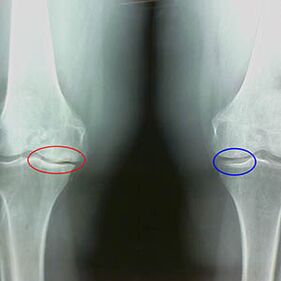

The degree of arthrosis is determined by x -GayExploring participation in the abnormal process of bone structures.Their change indicates that the musculoskeletal system was imbalanced for 5-10 years.As a general rule, peopleHave been experiencing painful pain for several yearsOr

The second stage of arthrosis is considered light.X -rays detect significant bone dots, but does not affect the cartilage.The amount of synovial fluid decreases, but the symptoms of pain occur after a long walk and run, the stiffness of the joint and the pain when bending and in the knees.

Characteristics of early X phase of the second stage of knee arthrosis:

- On the tibia, the pointed edges of the inter -writing tubers, where the cross -shaped ligament is fixed;

- Narrowing the common gap on the medial side;

- Condyles points of the bones on the medial sides, less often sideways - depending on the development of the valgus or variation joint deformation.

In the second stage of LarsenIt is typical, but this can only be checked in dynamics or comparison with a different joint.

Signs of moderate arthrosis of the knee joint in the third stage:

- The joint gap was significantly narrowed;

- the presence of subchondral sclerosis in the stages of filled;

- Many osteophys on the edges;

- a rare appearance of subchondral cysts;

- Synovites, baker cyst appearance under knee;

- Uneven surfaces of the femur and tibia, loss of joint joints;

- Change in the form of patella;

- Focus on calcification and condomation;

X -rays show the presence of osteophytes, a change in space between femoral and tibia bones, which indicates the loss of cartilage in the knee.Occasionally the X -scrub of knee joints show significant signs of cartilage wear, but patients do not suffer significant pain.On the contrary, the arthrosis of the first stage may interfere with the function of the kneeBecause the pain is caused by hypotonic muscles.